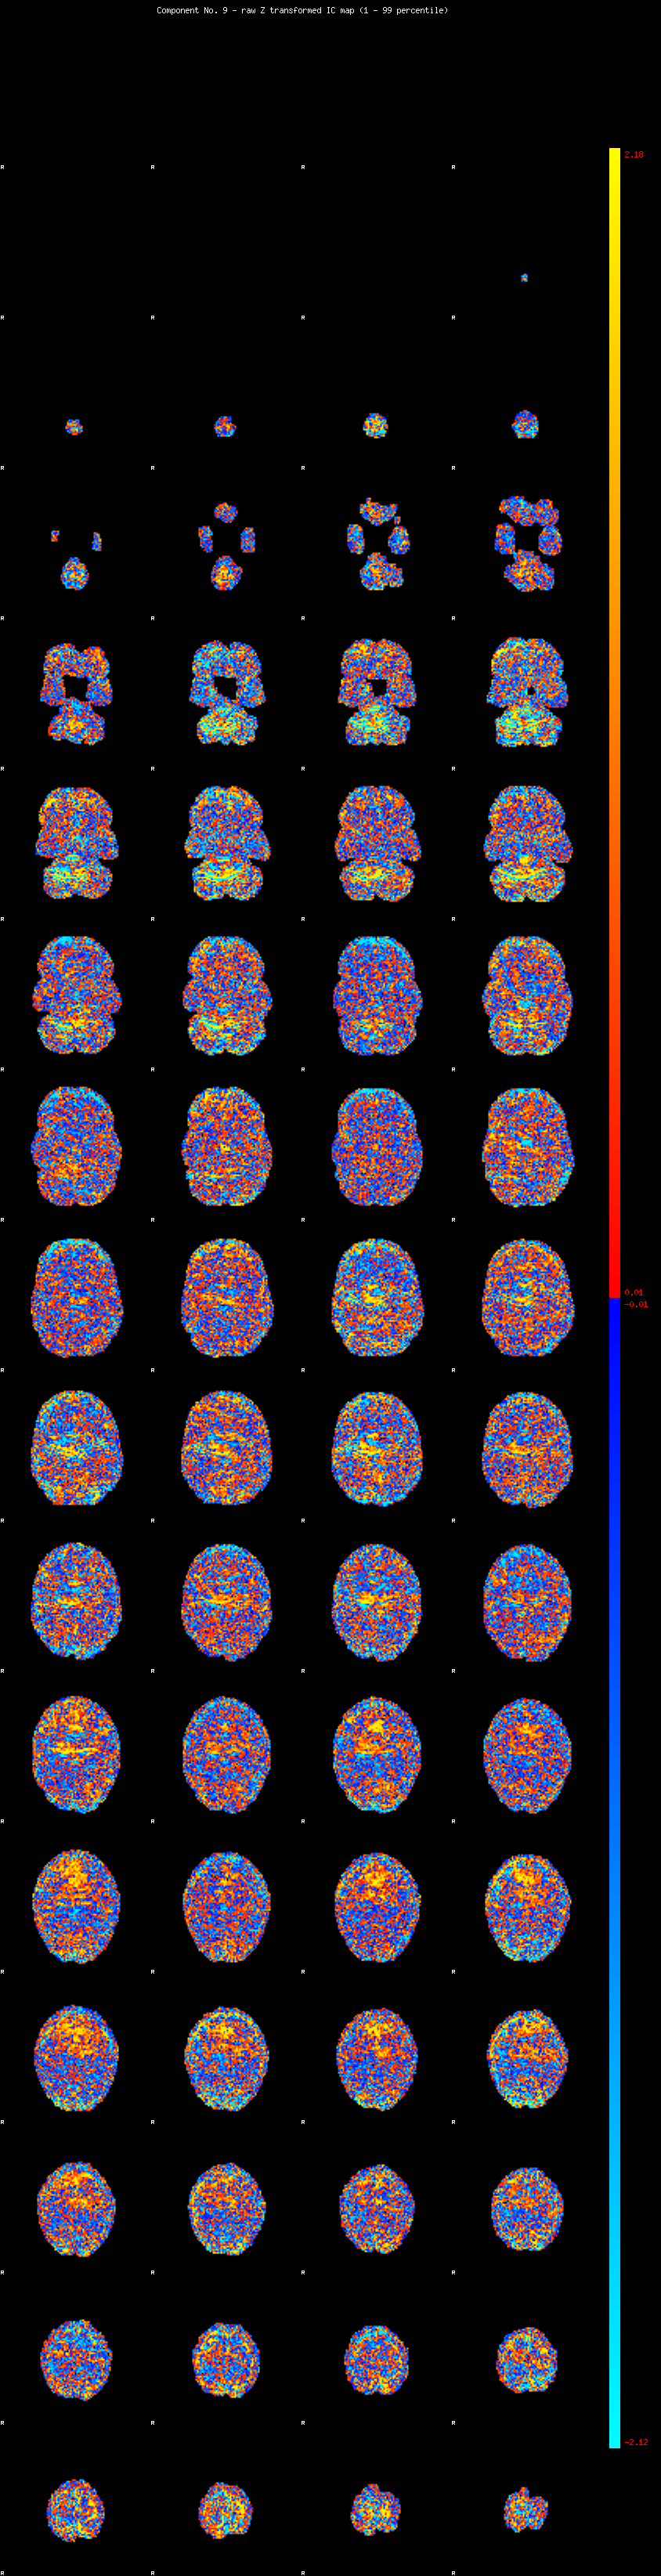

IC_9 Mixture Model fit

Means : 0.000000 2.297707 -2.273184

Vars : 1.000000 1.341158 1.289346

Prop. : 0.890360 0.057829 0.051811